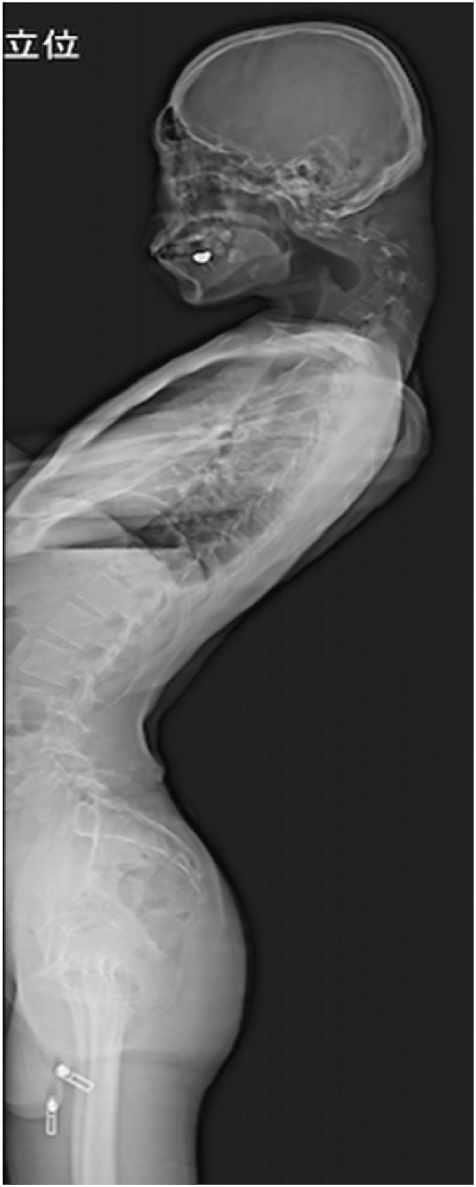

수술 후 6개월 만에 환자는 머리를 수평으로 쉽게 유지할 수 있게 됐다. 그 결과 음식을 삼키는 어려움도 없어져 식사를 정상적으로 할 수 있게 됐고, 전반적인 자세와 삶의 질이 크게 개선됐다.

수술 후 호전된 척추와 목뼈 상태. 일본정형외과 학회지(JOS)의 사례 연구집 논문 캡처

퇴원 후 스마트폰 게임을 하는 습관은 다시 이어졌으나 1년 뒤 추적 관찰한 결과 전과 같은 심각한 목 꺾임은 재발하지 않았다.